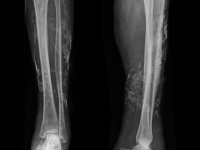

![Calcinosis cutis bij chronische veneuze insufficientie (click on photo to enlarge) [source: www.huidziekten.nl] Calcinosis cutis bij chronische veneuze insufficientie](../../../images/calcinosis-cutis-1z.jpg) |

![Calcinosis cutis bij chronische veneuze insufficientie (click on photo to enlarge) [source: www.huidziekten.nl] Calcinosis cutis bij chronische veneuze insufficientie](../../../images/calcinosis-cutis-2z.jpg) |

![Calcinosis cutis bij chronische veneuze insufficientie (click on photo to enlarge) [source: www.huidziekten.nl] Calcinosis cutis bij chronische veneuze insufficientie](../../../images/calcinosis-cutis-3z.jpg) |

| calcinosis cutis bij CVI |

calcinosis cutis bij CVI |